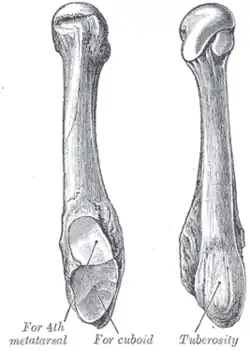

Anatomy of the fifth metatarsal.

Anatomy of the fifth metatarsal. 3 zone description

3 zone description 2 zone description

2 zone description